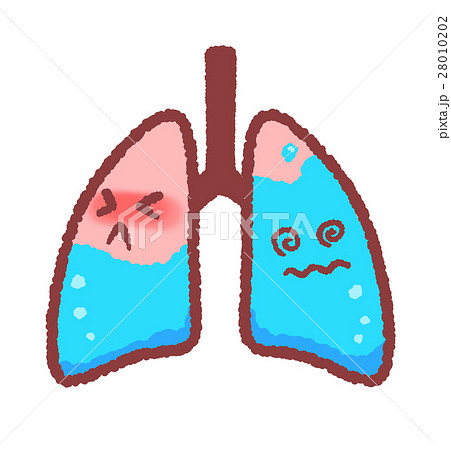

水が溜まった肺のイラスト素材

不健康 肺 水が貯まる イラスト イラスト素材 フォトライブラリー Photolibrary

肺水腫のイラスト素材

肺水腫のイラスト素材